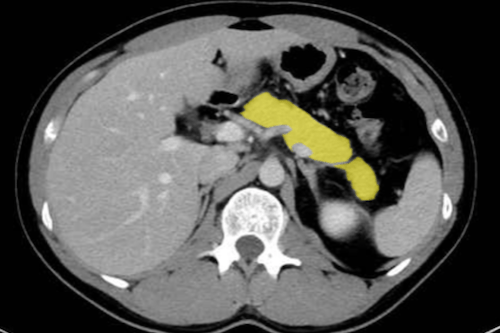

복부CT로 알 수 있는 질병

복부CT로 알 수 있는 질병들로는 간, 담낭, 췌장, 신장, 비장, 위장관, 복부 혈관까지 폭넓게 관찰할 수 있습니다. 특히 소화기 종양 진단이나 응급 복통 원인 파악에 중요한 역할을 합니다.

2. 담낭 및 췌장 질환

- 췌장암: 조기 발견이 어렵지만 CT에서 종괴, 췌관 확장 소견으로 추정 가능.

- 급성·만성 췌장염: 췌장의 염증, 괴사, 석회화 여부를 확인 가능.